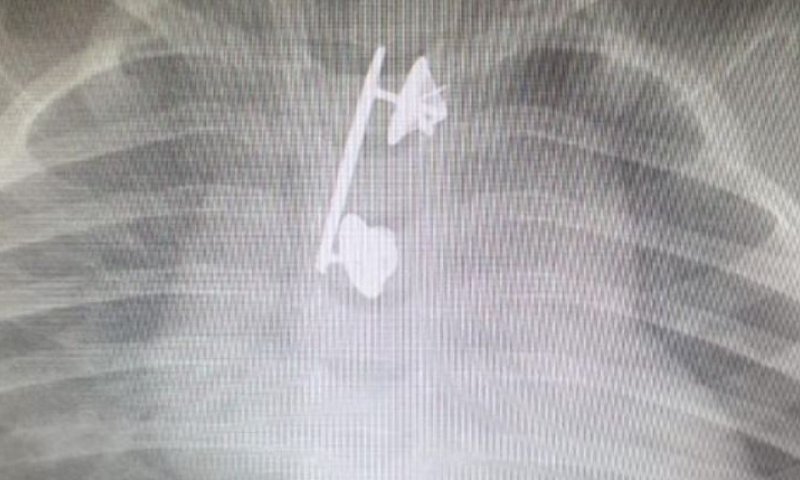

זוג הורים, קצינים בצה"ל, הבהילו לאחרונה את בנם בן ה- 10 חודשים לבית החולים 'קפלן' אחרי שחש ברע, התקשה בפעולת הבליעה ואף הקיא דם. לאחר צילום רנטגן הרופאים גילו: סיכת המ"מ של האם תקועה בוושת שלו

ההורים המודאגים פינו אותו לבית החולים, שם למרבה התדהמה, התגלה לאחר צילום רנטגן כי בוושת שלו תקועה סיכת מ"מ של אימו הקצינה. הסיכה הוצאה בניתוח והתינוק שוחרר לביתו לאחר מספר ימים.

ד"ר מיכל קורי וד"ר מאיר וורמן, שני הרופאים ששלפו בהצלחה את הגוף הזר מהוושט, סיפרו: "כאשר נתגלתה סיכת המ"מ בצילום היה ברור שהפרוצדורה תהיה מאוד מורכבת בשל הגודל והחדות של שלה. העובדה שהסיכה הוצאה בזמן מנעה סיכונים שעלולים להיגרם במקרים אלו כגון קרע של הושט, זיהום וקשיי בליעה. אין ספק שערנות ההורים במקרה זה הייתה בעלת חשיבות רבה".